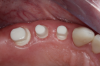

Fig 6. After splint removal (12 weeks postoperatively).

Figure 6

Fig 7. 12 weeks postoperatively.

Figure 7